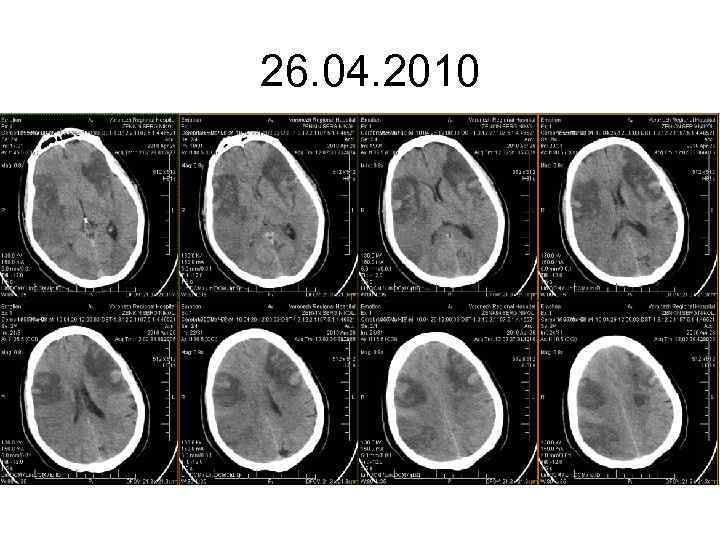

26. 04. 2010